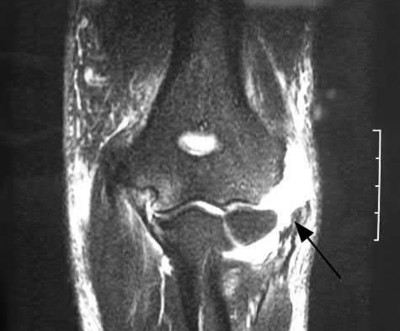

This patient has a posterior knee dislocation with an ischemic limb that does not reverse following reduction. Emergent vascular exploration and reconstruction is indicated.

Knee dislocations are associated with popliteal artery injury in 18-45% of cases and range from intimal tears to complete transection. Amputation rates of 85% have been reported if revascularization is delayed greater than 6 to 8 hours.

Neurologic injury occurs in 15-40% of cases and is most common after posterolateral dislocation. The peroneal nerve is more commonly injured.

Rihn et al. reviewed the acutely dislocated knee. They recommend a vascular consult if pulses are weak, or ABI is compromised. They warn that in arterial injury, pulses, temperature and capillary refill can be normal. If the limb remains ischemic, surgical exploration and revascularization is indicated.

Medina et al. systematically reviewed neurovascular injury after knee dislocation in 862 patients. Vascular injury rate was 18%, and nerve injury rate was 25%. Repair was performed in 80% of vascular injuries, and amputation in 12%. The most vascular injury was seen in KDIIIL injuries (32%) and posterior dislocation (25%).

Figure A is an AP radiograph of a posterior knee dislocation. Figure B is a lateral showing the same injury.